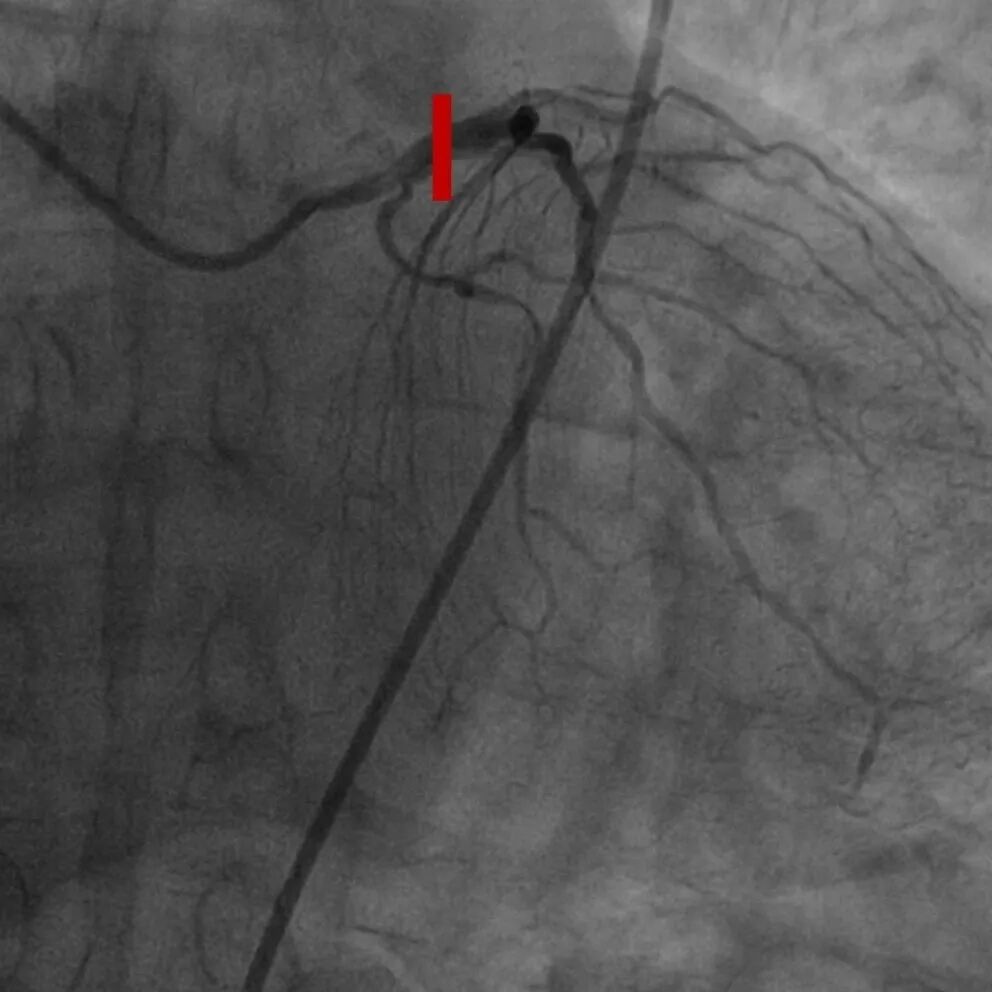

正向选择2.5 OTW球囊,Pilot200尝试开通

选择平行导丝:KDL+Pilot200、Gaia3、CP12、8-20

尝试逆向:150 Finecross+SionBlack、Suoh 03

侧枝极为迂曲,不完全连

再转正向:Corsair+XT Knucle

再转正向:CP 12、Pilot 200

再转正向:Pilot 200

于RCA中段选择shockwave 3.5x12mm,8个周期

选择3.5mm后扩球囊,22-24atm扩张

于RCA植入三枚支架:3.0、3.5、4.0